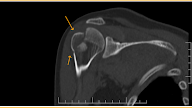

- Stress fractures are of two varieties (a) superior surface involvement called tension fractures can and do progress and displace (b) Inferior surface fracture called compression variety is stable and shows callus on all modalities usually

- MRI is good modality to show linear fracture line and marrow edema on either side . Bone scan is also diagnostic like other locations in cases of stress fracture including occult variety